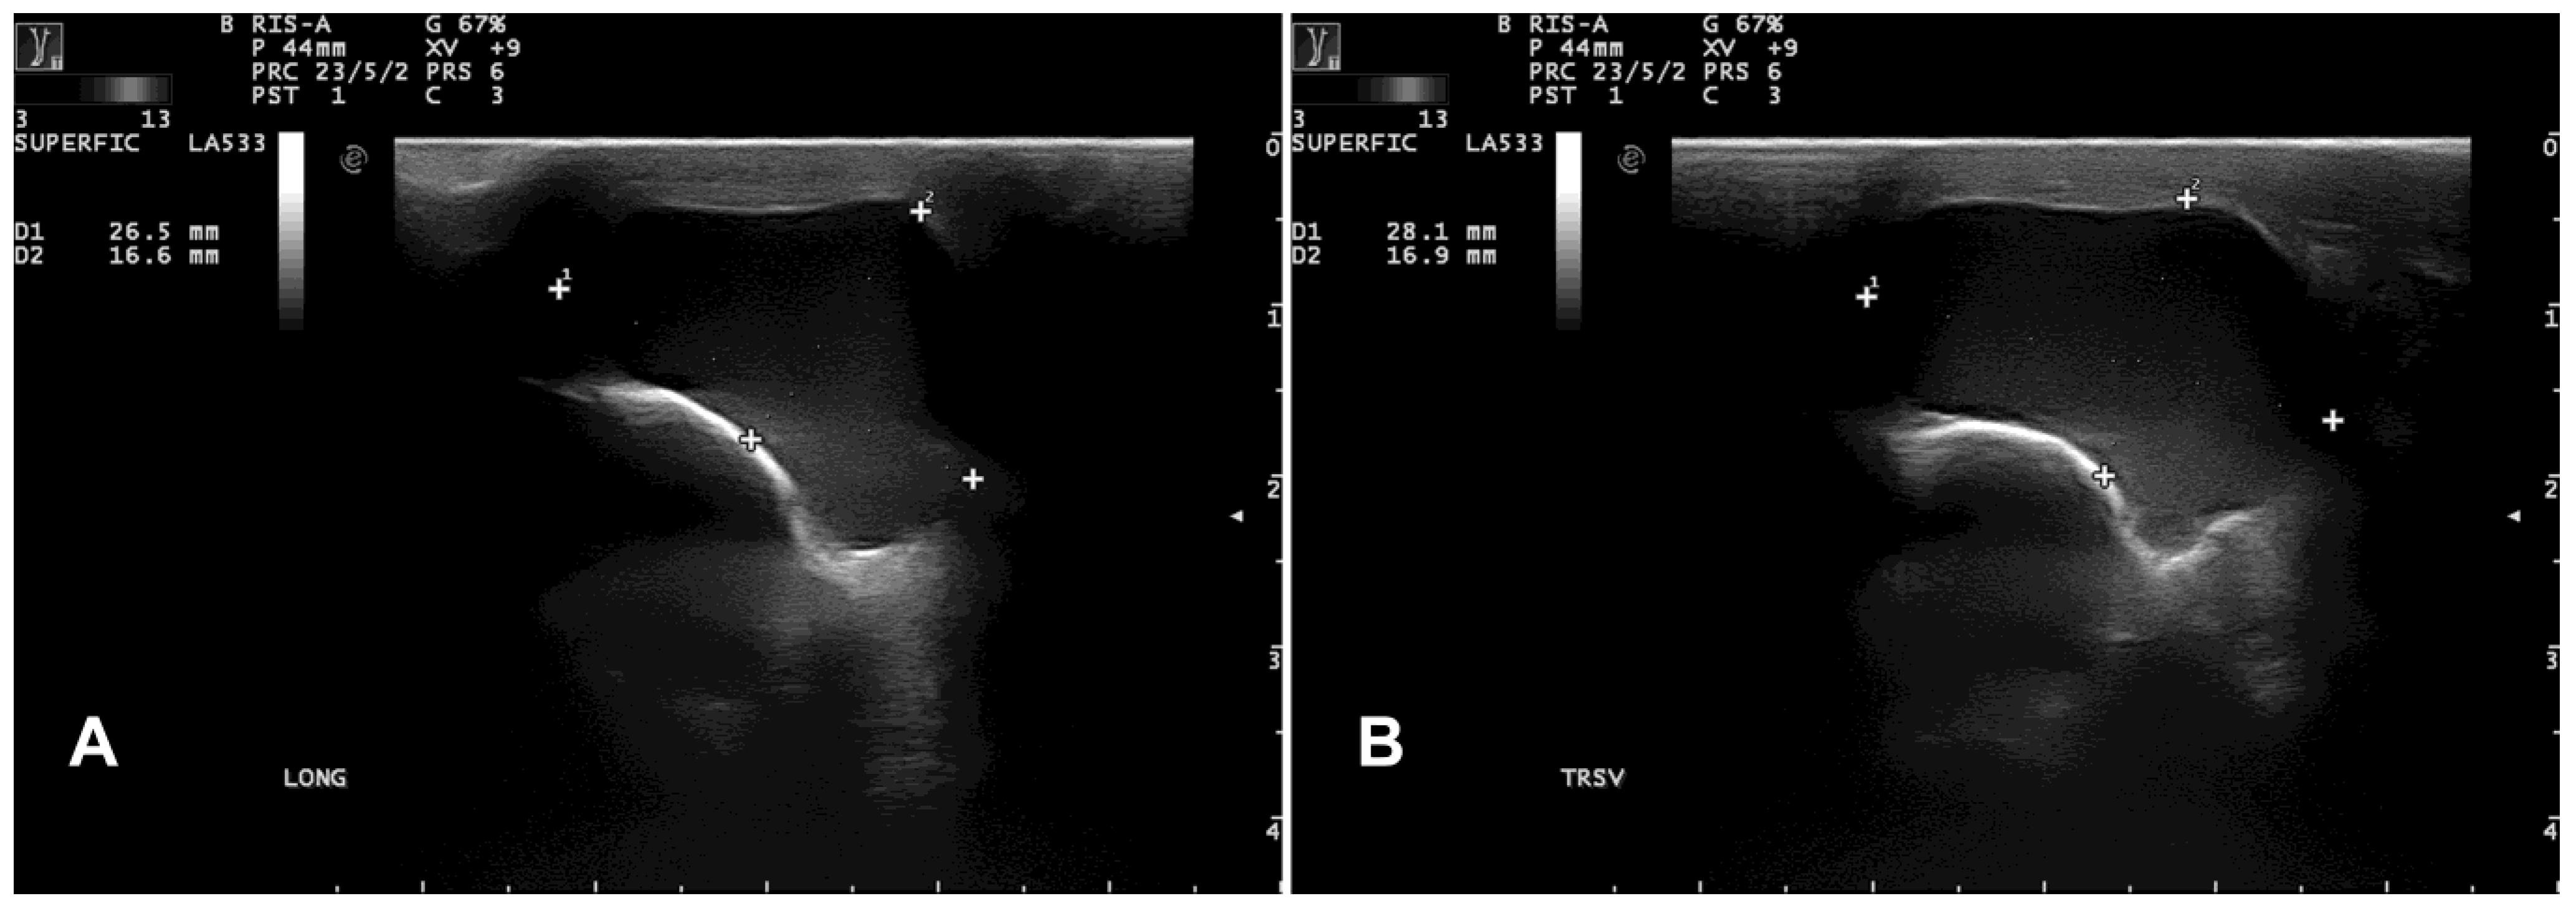

B-mode ultrasonography revealed a subcutaneous cyst characterized by a hypoechoic content lined by a thin wall (Figure 3).

Figure 3. Case 1: longitudinal (A) and transversal (B) ultrasonographic images of a thin-walled cystic structure (enclosed by the dotted electronic callipers) containing finely echogenic, fluctuating material.